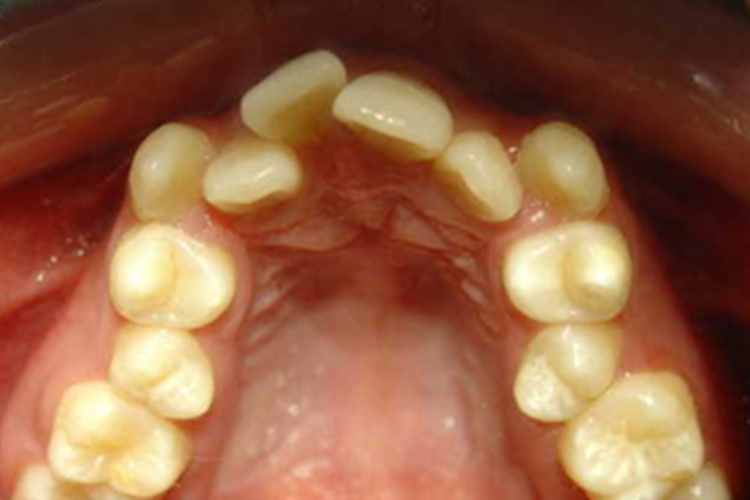

错颌畸形可表现可为牙齿的排列异常,如扭转、倾斜、里出外进或拥挤错乱等,也有人虽然牙齿排列整齐,但上下牙的咬颌关系异常,出现上牙弓前突(俗称“大呲牙”)或下牙弓前突(俗称“地包天”)等。严重的情况会引起面部形态的异常,导致面部外观看起来呈月牙形。